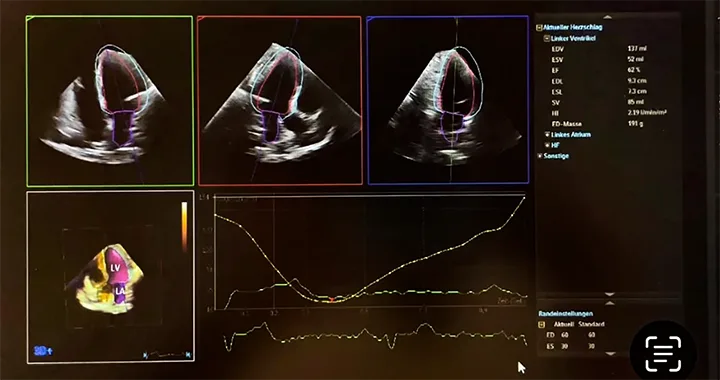

3D-basierte Bestimmung der Ejektionsfraktion (EF)

Volumetrische, automatisierte Messung der links- und rechtsventrikulären Pumpfunktion – objektiv, reproduzierbar und klinisch aussagekräftiger als herkömmliche 2D-Verfahren. Ermöglicht eine präzise Beurteilung der Herzleistung bei Herzinsuffizienz, Kardiomyopathien und pulmonaler Hypertonie.